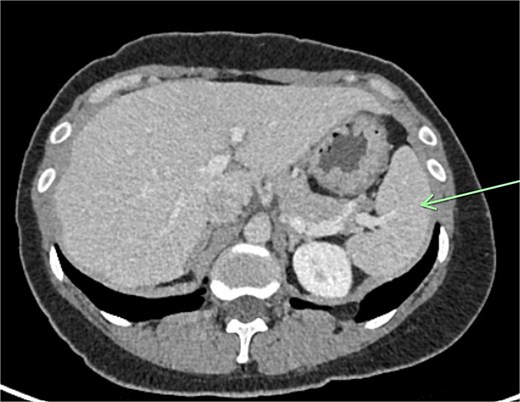

The aforementioned CT was reassessed intraoperatively together with this new information. The vascular pedicle was traced from the lesion towards the splenic vessels at the tail of the pancreas. A normal spleen was identified in the left upper quadrant (Figs 3–5). The overall impression was that this lesion represented accessory splenic tissue. The general surgery team called the patient’s next of kin, who gave consent to proceed with an excision of this wandering accessory spleen.

A firm solid well-circumscribed 6 cm lesion was identified in the right upper quadrant. The general surgery team was contacted for intraoperative consultation. This lesion appeared to be mobile and attached to a long vascular pedicle which was followed to the left upper quadrant, where it passed over the transverse colon towards the splenic hilum (Figs 1 and 2).

The spleen is a foregut-associated structure located under the diaphragm in the left upper quadrant of the abdominal cavity. While it is not a direct derivative of the foregut, it shares the same blood supply as the foregut-derived organs – the coeliac axis. The spleen develops from the mesenchyme in the dorsal mesogastrium as a condensation of these cells. As a result of this embryogenic process, it is susceptible to the development of accessory spleens, wandering spleen, and polysplenia.